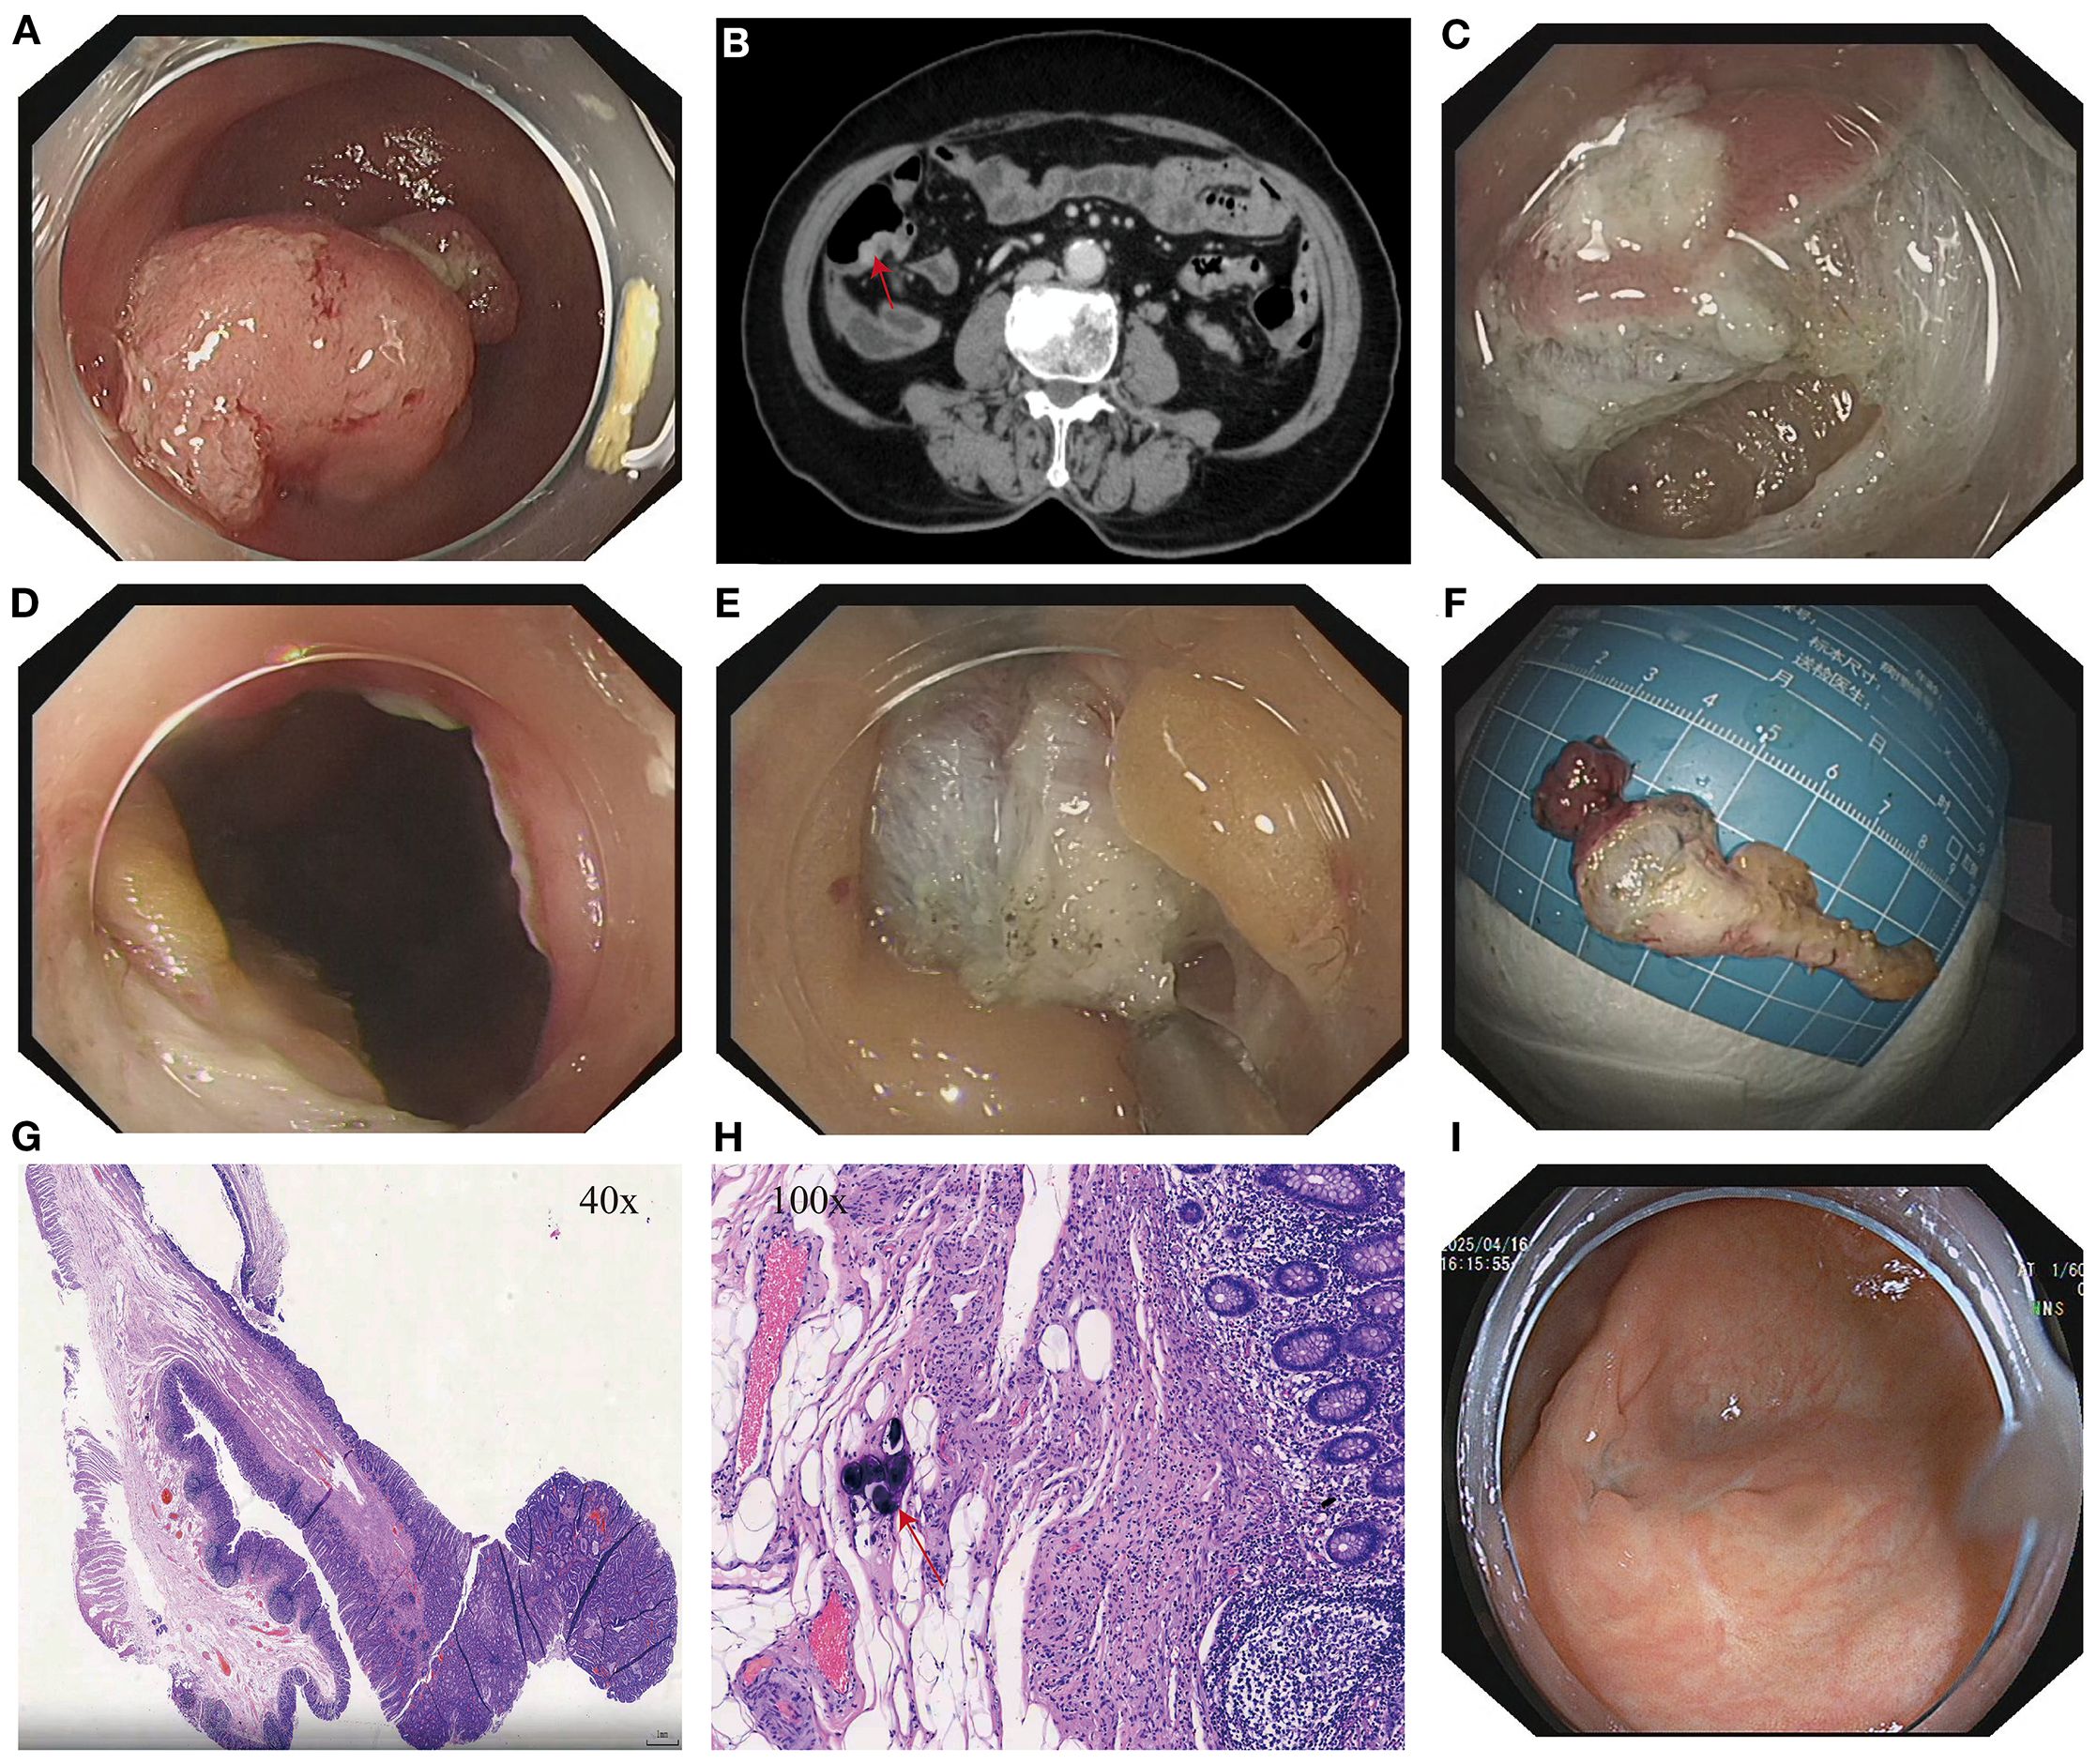

Figure 1. (A) Lesion at the appendiceal orifice. (B) Contrast-enhanced abdominal CT showing a nodular lesion in the cecum with a tegument-like structure extending into the appendix (red arrow). (C) Intraoperative incision during ETA procedure. (D) Entry into the abdominal cavity during ETA. (E) Dissection of the appendix and surrounding tissues. (F) Resected appendiceal specimen following ETA. (G) Histopathological findings of the appendiceal lesion. (H) Calcified Schistosoma haematobium eggs (red arrows) observed under high-power magnification in the appendix following ETA. (I) Follow-up colonoscopy at 15 months showing a well-healed surgical scar at the cecum with no evidence of recurrence or stenosis.

After thorough evaluation confirmed no contraindications to endoscopic surgery, the patient underwent ESD of the sigmoid colon tumor (Figure 2). The lesion was completely resected, and the endoscope was able to smoothly advance through the previous site to reach the ileocecal region. At the appendiceal orifice, a tumor-like lesion protruding from the lumen was identified, biopsied, and sent for pathological examination (Figure 1A). Postoperative pathology of the sigmoid colon lesion confirmed a tubular adenoma, with calcified Schistosoma egg deposits in the submucosal layer at the tip (Figure 2F). The biopsy of the appendiceal lesion indicated adenomatous changes.

After the procedure, hematochezia resolved, and the patient’s clinical symptoms improved. However, the lesion at the appendiceal orifice showed adenomatous changes and required further intervention. The conventional treatment approach—surgical resection of the appendix with ileocecal and partial small bowel resection—is highly invasive, associated with delayed postoperative recovery, and carries risks such as abdominal wall infection, postoperative pain, incisional hernia, and prolonged hospitalization, especially in elderly patients (10–12). After thorough communication with the patient and her family, and obtaining informed consent, our team performed ETA, achieving complete resection of the appendix and associated lesion (Figure 1). Postoperatively, the patient was managed with two days of fasting, bed rest, anti-infective therapy, and symptomatic supportive care. Recovery was uneventful.

Postoperative pathology confirmed that the appendiceal orifice lesion was an adenomatous polyp with high-grade intraepithelial neoplasia. Calcified Schistosoma eggs and chronic inflammatory changes were observed in the mucosa at the tip (Figure 1H). The patient experienced no postoperative abdominal pain, hematochezia, or fever, and was discharged one week after surgery in good general condition. Physical examination revealed no abdominal tenderness or rebound pain.

A colonoscopy performed 15 months after surgery revealed a well-healed surgical scar in the ileocecal region, with no evidence of recurrence or intestinal stenosis (Figure 1I).